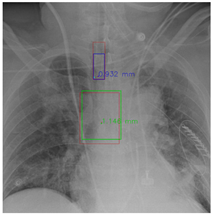

4.5.7. The Post-Process Algorithm

Figure 7 and Figure 8 demonstrate the effect of post-processing. The red bboxes and points in these figures are the GT ETT/bifurcation bboxes and the position of GT ETT tip/Carina, respectively. The green polygon is the GT mask of the ETT and the bifurcation. The blue bbox and point are the predicted ETT bbox and ETT tip, respectively. The yellow bbox and point are the predicted bifurcation and Carina, respectively. Specifically, without the post-process, the model might leave more than one predicted ETT tip/Carina, such as where the red arrow points in Figure 7a. However, with the post-process, the extra points would be removed as shown in Figure 7b. Besides, with the refinement process in the post-process, the feature point of ETT tip/Carina could be further refined as shown in Figure 8. Concretely, the object error of Carina was corrected from 8.469 mm to 1.319 mm.

Figure 7. Ensuring at most one ETT tip/Carina left. (a) Without post-process. (b) With post-process.

Diagnostics 12 01913 g007